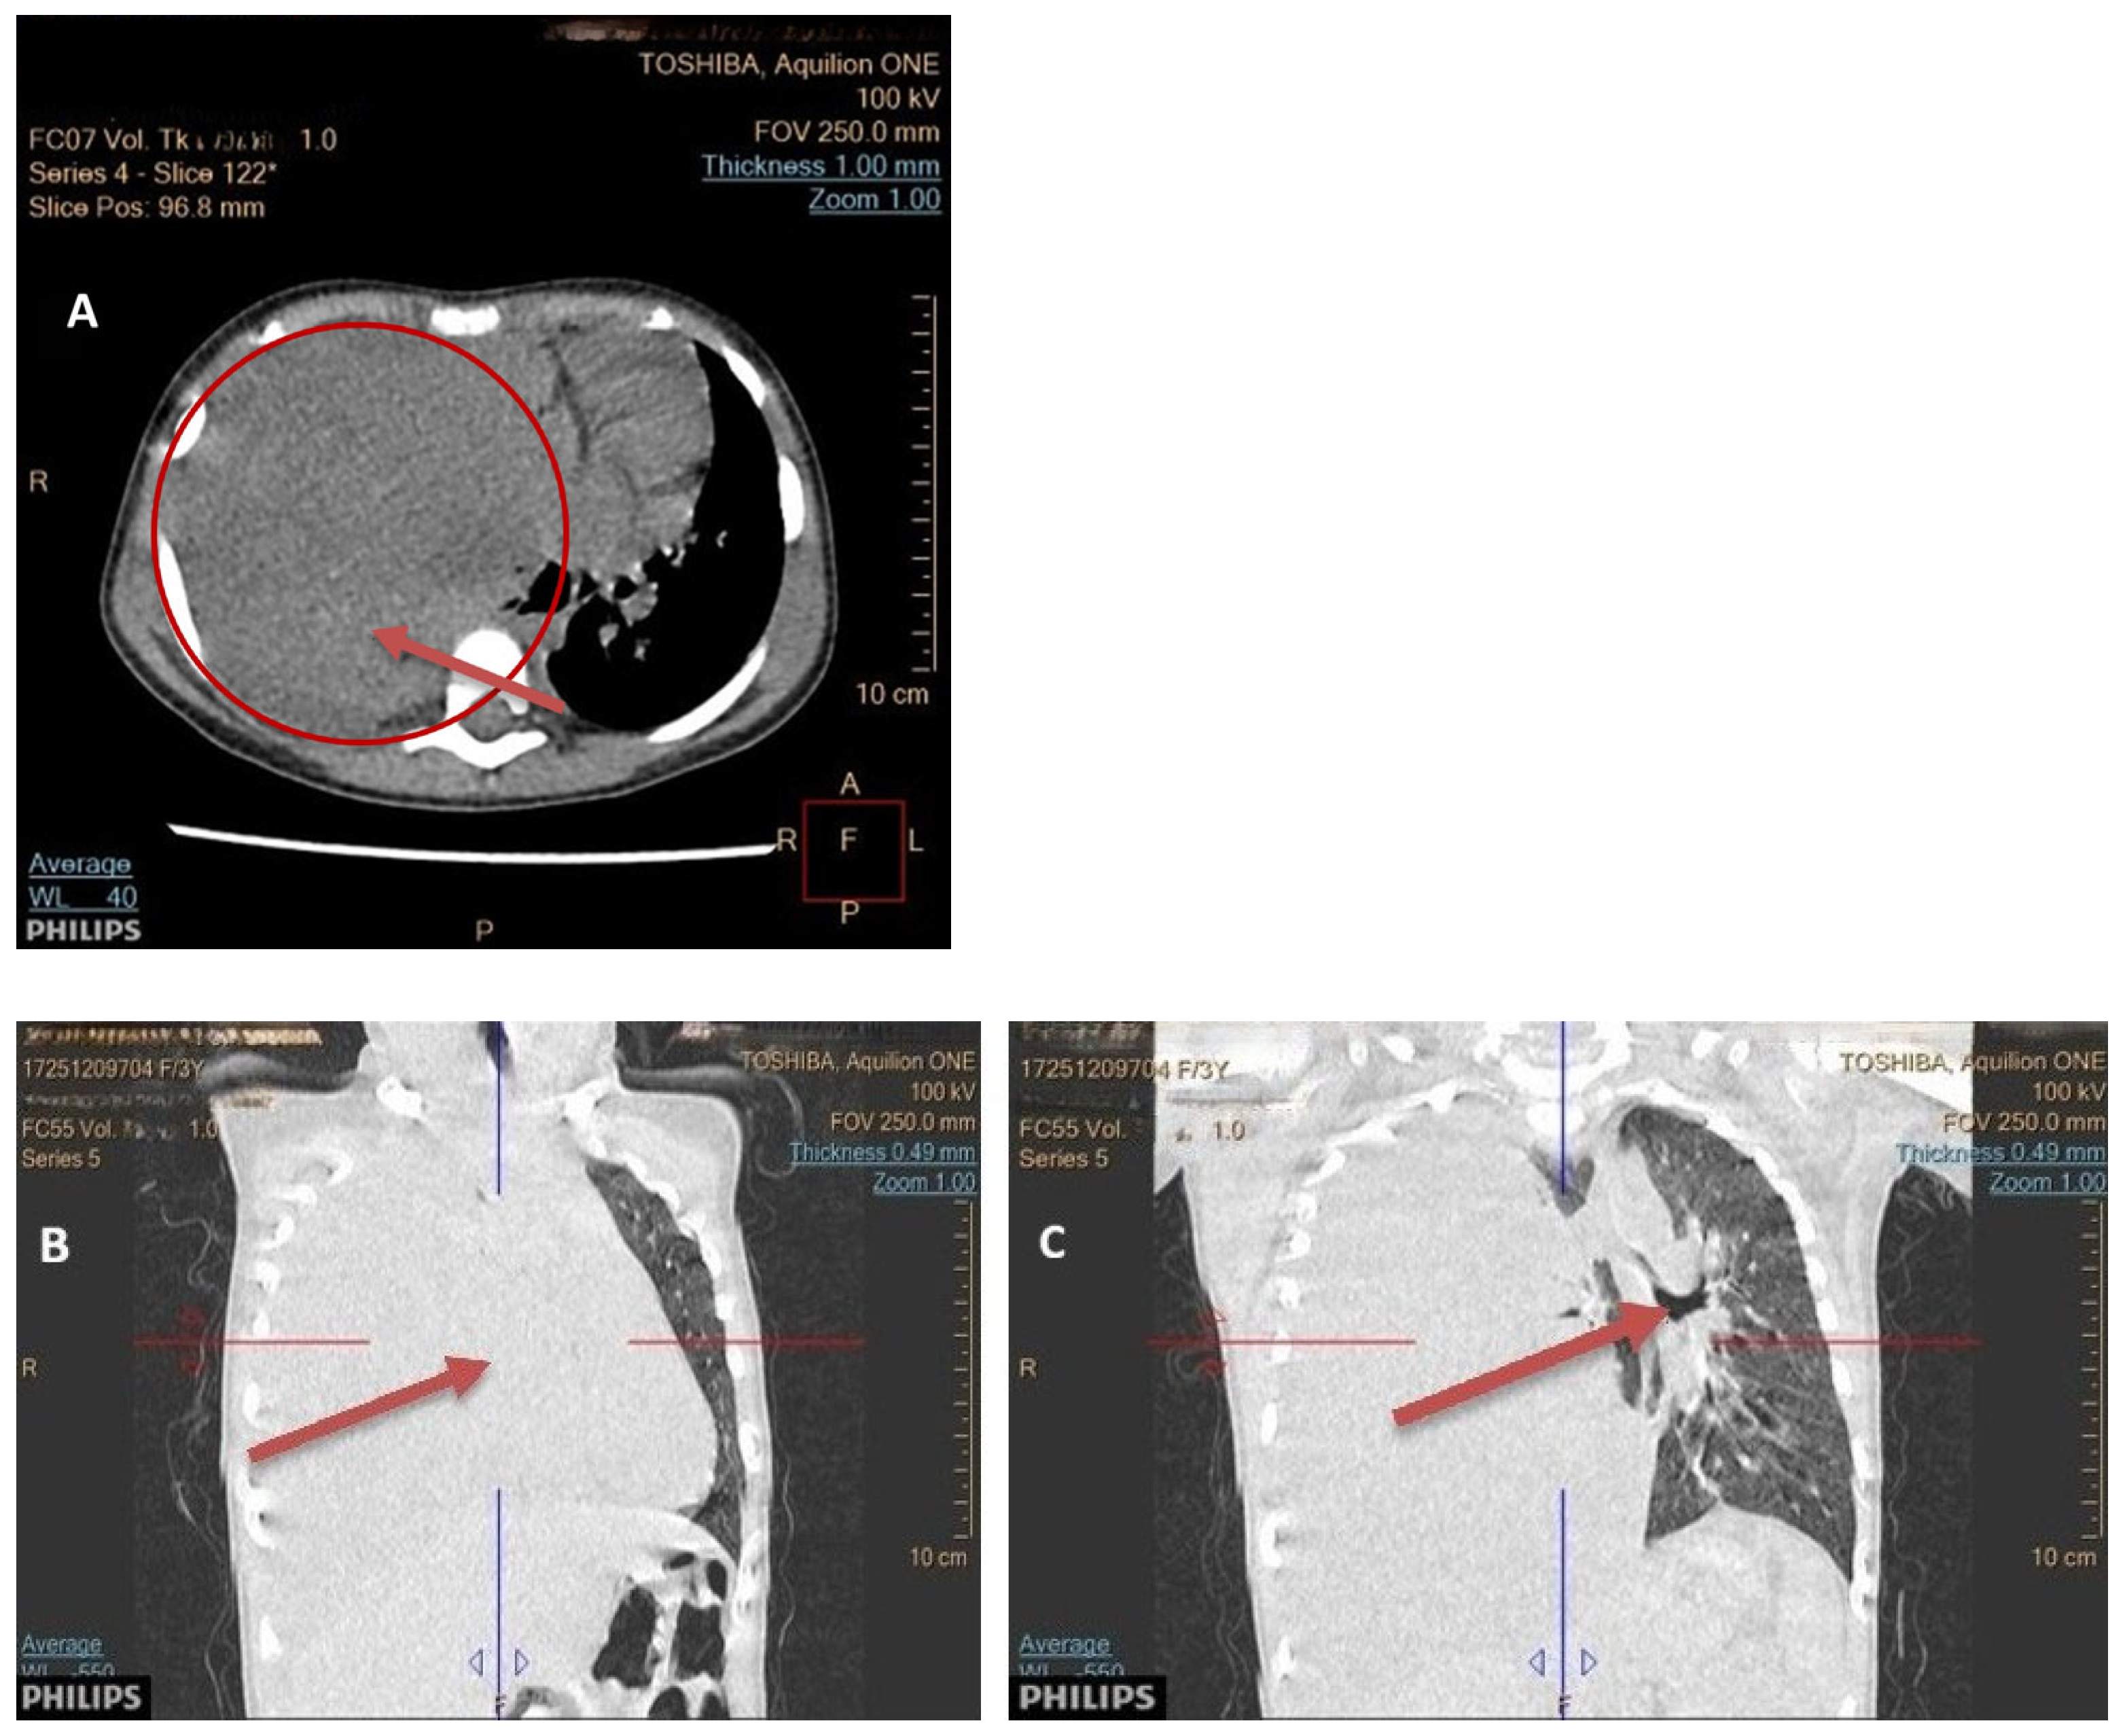

3.2. Diagnosis

3.4. Tumor Localization and Size